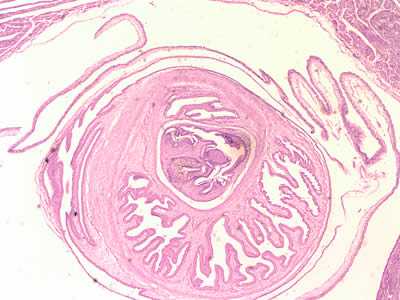

Larval Taenia solium.

Figure E: Cross-sections of cysticerci stained with H&E, at 40x magnification

Figure F: Cross-sections of cysticerci stained with H&E, at 100x magnification.